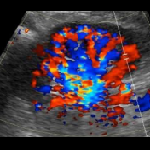

Renal Transplant on Ultrasound - Educational Content

- Renal Transplant on Ultrasound